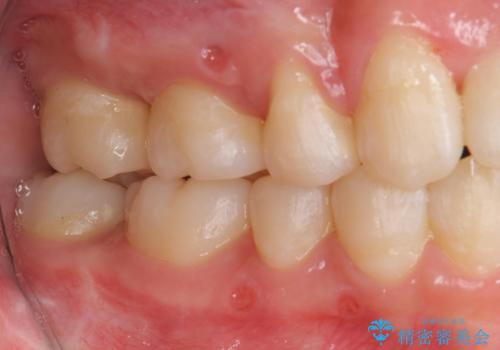

前歯は重度のがたつき、また奥歯はすれ違っていました。

上下の顎の幅もあっておらず、成人でしたが手術なしで上あごを骨から広げる処置(急速拡大装置)を行いました。